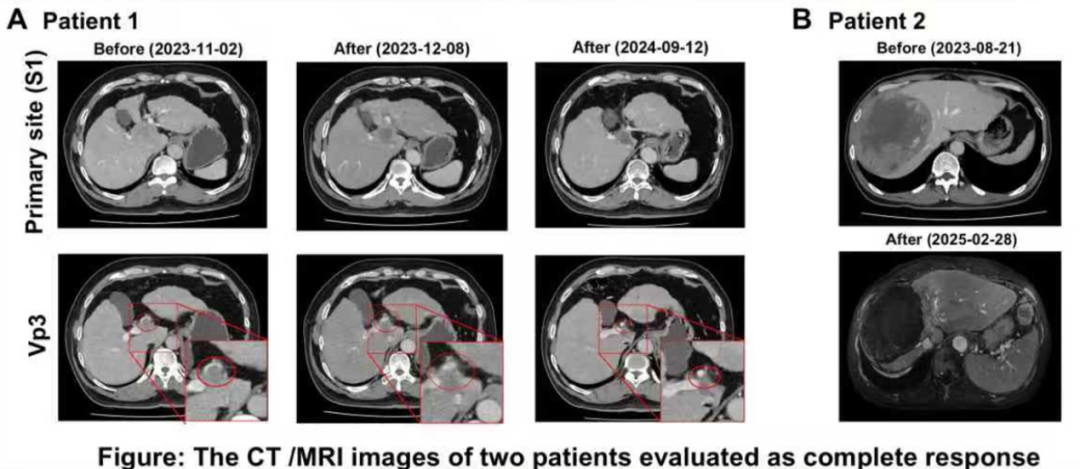

疗效评估:客观缓解率(ORR)达到85.7%(6/7),其中治疗区域的ORR更是高达100%。具体而言,完全缓解(CR)率为28.6%(2/7),这两例患者的CR状态持续了9个月;部分缓解(PR)率为57.1%(4/7)。仅1例患者(14.3%)出现疾病进展(PD)。

两例被评估为完全缓解患者的CT/MRI图像

安全性评估:没有患者出现3级及以上不良事件(AE)。最常见的不良事件是腹痛和呕吐,且所有并发症均可控。

90Y-SIRT联合Atezo-Bev治疗uHCC,展现出令人鼓舞的局部ORR(100%)和良好的安全性。这些初步发现有待未来在更大样本量的队列中进一步验证,以明确该联合方案的最佳治疗顺序及治疗时长,为临床实践提供更可靠的循证依据。